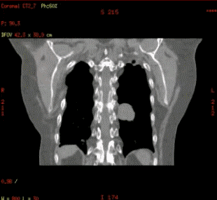

D4D可独立完成四维CT扫描,简化扫描流程效率更高